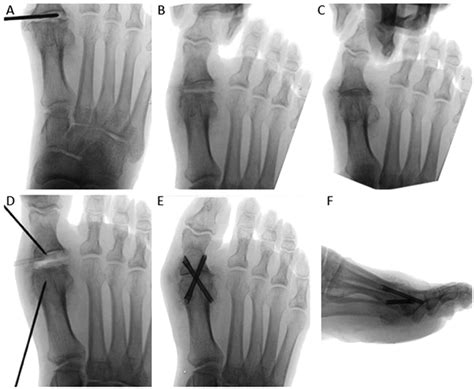

Diagnosing problems with the 1st MTP joint typically involves a combination of physical examination, medical history, and imaging tests. A healthcare professional will assess the joint's range of motion, tenderness, and any visible deformities. Imaging tests such as X-rays, MRI, or CT scans may be used to get a clearer picture of the joint's structure and identify any underlying issues.

Imaging tests provide detailed views of the joint and surrounding structures. X-rays can show bone abnormalities, while MRI and CT scans offer more detailed images of soft tissues, ligaments, and tendons.

• Cheilectomy: This procedure involves removing bone spurs or other obstructions that limit joint movement.

• Osteotomy: Realigning the bones to correct deformities and improve joint function.

• Arthrodesis: Fusing the joint to eliminate pain and improve stability, although this limits mobility.

• Arthroplasty: Replacing the damaged joint with an artificial implant to restore function and reduce pain.